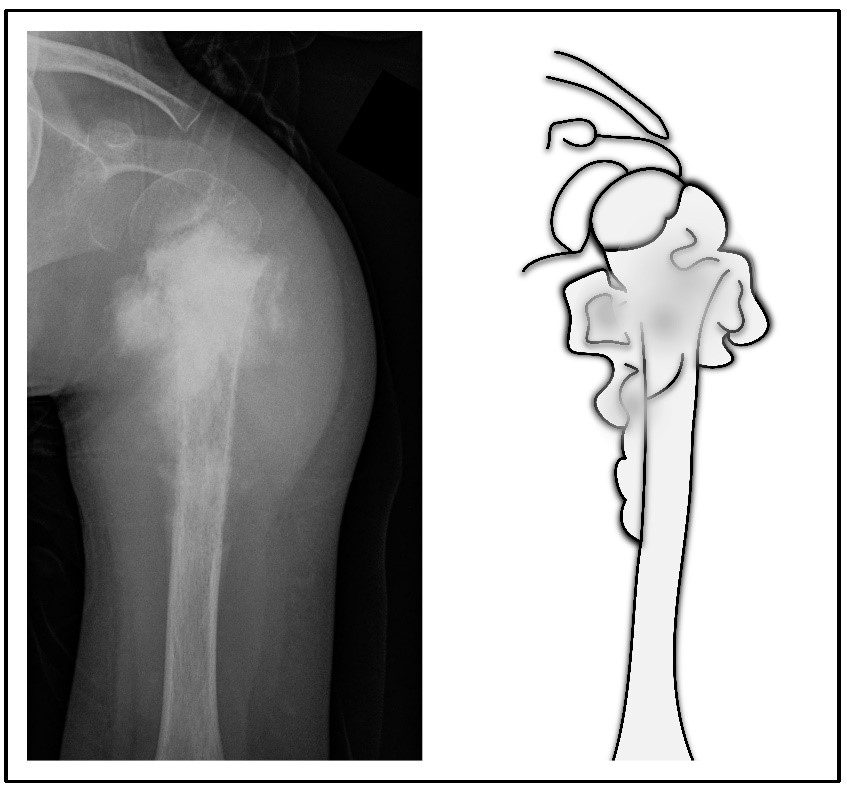

Abb. links: Röntgenbild eines Ewing-Sarkoms in einem Humerus (Oberarmknochen).

Abb. rechts: Schemazeichnung.